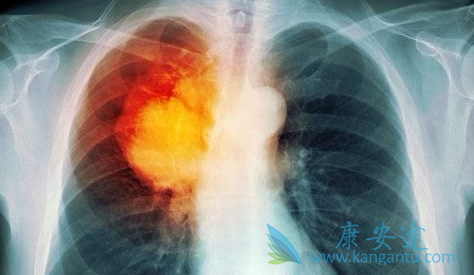

肺癌是全球恶性肿瘤中发病率和死亡率最高的一种,往往在被发现和确诊时都已经处于中晚期了,失去了手术根除肿瘤的机会,此时肺癌的治疗只能是以减轻患者的痛苦提高生存质量为首要任务。在我国表皮因子受体(EGFR)基因的突变是诱发肺癌的主要原因之一。不过随着靶向药物的问世,具有EGFR突变的非小细胞肺癌治疗也进入了精准时代,奥希替尼(AZD9291)就是其中重要的一员。